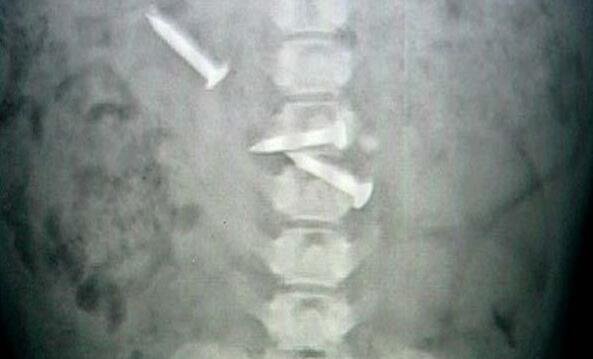

刚刚这货在和侄子玩的时候,肚子上就挂着一块磁铁,好像是侄子从家里自带的玩具,就紧紧的贴在狗狗的肚子上,这还了得?这说明狗狗的肚子里有铁质的东西,这样才会招磁铁的!

我立马就联想到这货肯定是吞了什么不该吞的东西了,于是赶紧送这货去了医院,果然,医生给狗狗做了手术之后,发现了一大堆乱七八糟的东西,其中有就有铁钉。

医生看了之后判断说狗狗吞下的时间还不长,要是等到发病之后再送来,还真心就危险了。真心是佩服我家狗狗了,真的是什么都敢吃啊!